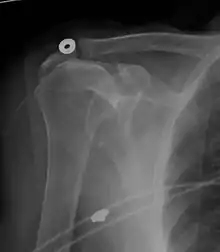

Xray

X-ray projectional radiography cannot directly reveal tears of the rotator cuff, a 'soft tissue', and consequently, normal X-rays cannot exclude a damaged cuff. However, indirect evidence of pathology may be seen in instances where one or more of the tendons have undergone degenerative calcification (calcific tendinitis). The humeral head may migrate upwards (high-riding humeral head) secondary to tears of the infraspinatus, or combined tears of the supraspinatus and infraspinatus.[46] The migration can be measured by the distance between:

- A line crossing the center of a line between the superior and inferior rims of the glenoid articular surface (blue in image).

- The center of a "best-fit" circle positioned over the humeral articular surface (green in image)

Normally, the former is positioned inferiorly to the latter, and a reversal is therefore indicating a rotator cuff tear.[46] Prolonged contact between a high-riding humeral head and the acromion above it, may lead to X-rays findings of wear on the humeral head and acromion and secondary degenerative arthritis of the glenohumeral joint (the ball and socket joint of the shoulder), called cuff arthropathy, may follow.[45] Incidental X-ray findings of bone spurs at the adjacent acromioclavicular joint may show a bone spur growing from the outer edge of the clavicle downwards towards the rotator cuff. Spurs may also be seen on the underside of the acromion, once thought to cause direct fraying of the rotator cuff from contact friction, a concept currently regarded as controversial.